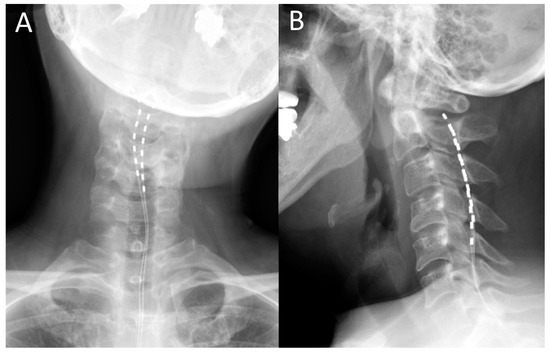

The surgery was performed under local anesthesia. For the trial, two Octrode® leads (Abbott Medical, Plano, TX, USA) were inserted percutaneously into the epidural space of the spine under X-ray radioscopy. The upper edges of both electrodes were finally positioned slightly lateral to the midline at the C2 level after obtaining the stimulation-induced paresthesia over the region of dystonic pain (Figure 1). During the trial period, a pulse generator was connected to the electrodes outside the body to conduct burst stimulation SCS. The stimulation parameters comprised the delivery of five spikes at 500 Hz, 40 times per second, with a pulse width of 1000 μS. The stimulation intensity was set to 50% of the sensory threshold. The combination of stimulation electrodes was changed daily to determine optimal stimulating paradigms to achieve the best pain relief. On the last day of the 7-day trial period, the percutaneous trial leads were removed. A few weeks after the trial period, the patients underwent permanent implantation of a pulse generator and two Octrode® leads (Abbott Medical, Plano, TX, USA) through the same procedure used in the trial stimulation under local anesthesia. The parameters for stimulation were set to those used to achieve optimal stimulation in the trial periods. Burst SCS was continuously performed during the follow-up periods. The position of the leads was confirmed by X-ray on the day after the operation and at least once a year during the follow-up period.

Figure 1.

Postoperative cervical X-ray images following spinal cord stimulation. (A) Anteroposterior and (B) lateral view.